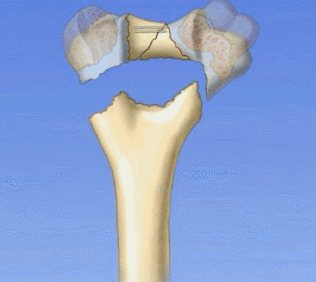

1.解剖中比较重要的就是柱的概念,分为外侧柱和内侧柱,一个重要的滑车结构包含了300度的关节面,在外侧有一个肱骨小头的结构,然后一个冠突窝的结构

2.其中有几个重要的角度,4-8度的轻微外翻角,30度前方的前倾角

肱骨的内外侧柱和滑车构成了一个三角形稳定结构,手术复位的时候一定要完成稳定三角结构的恢复。

肱骨远端复位原则:先柱还是先关节面?

理论上是滑车first!有的时候也可以先复位简单的。先复位滑车,是功能保证,那300度的关节面的复位需要达到解剖,加压!然后再进行柱的复位